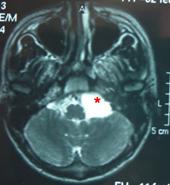

Resim 10: beyin sapı-beyincik bileşkesinde araknoid kist (

*).